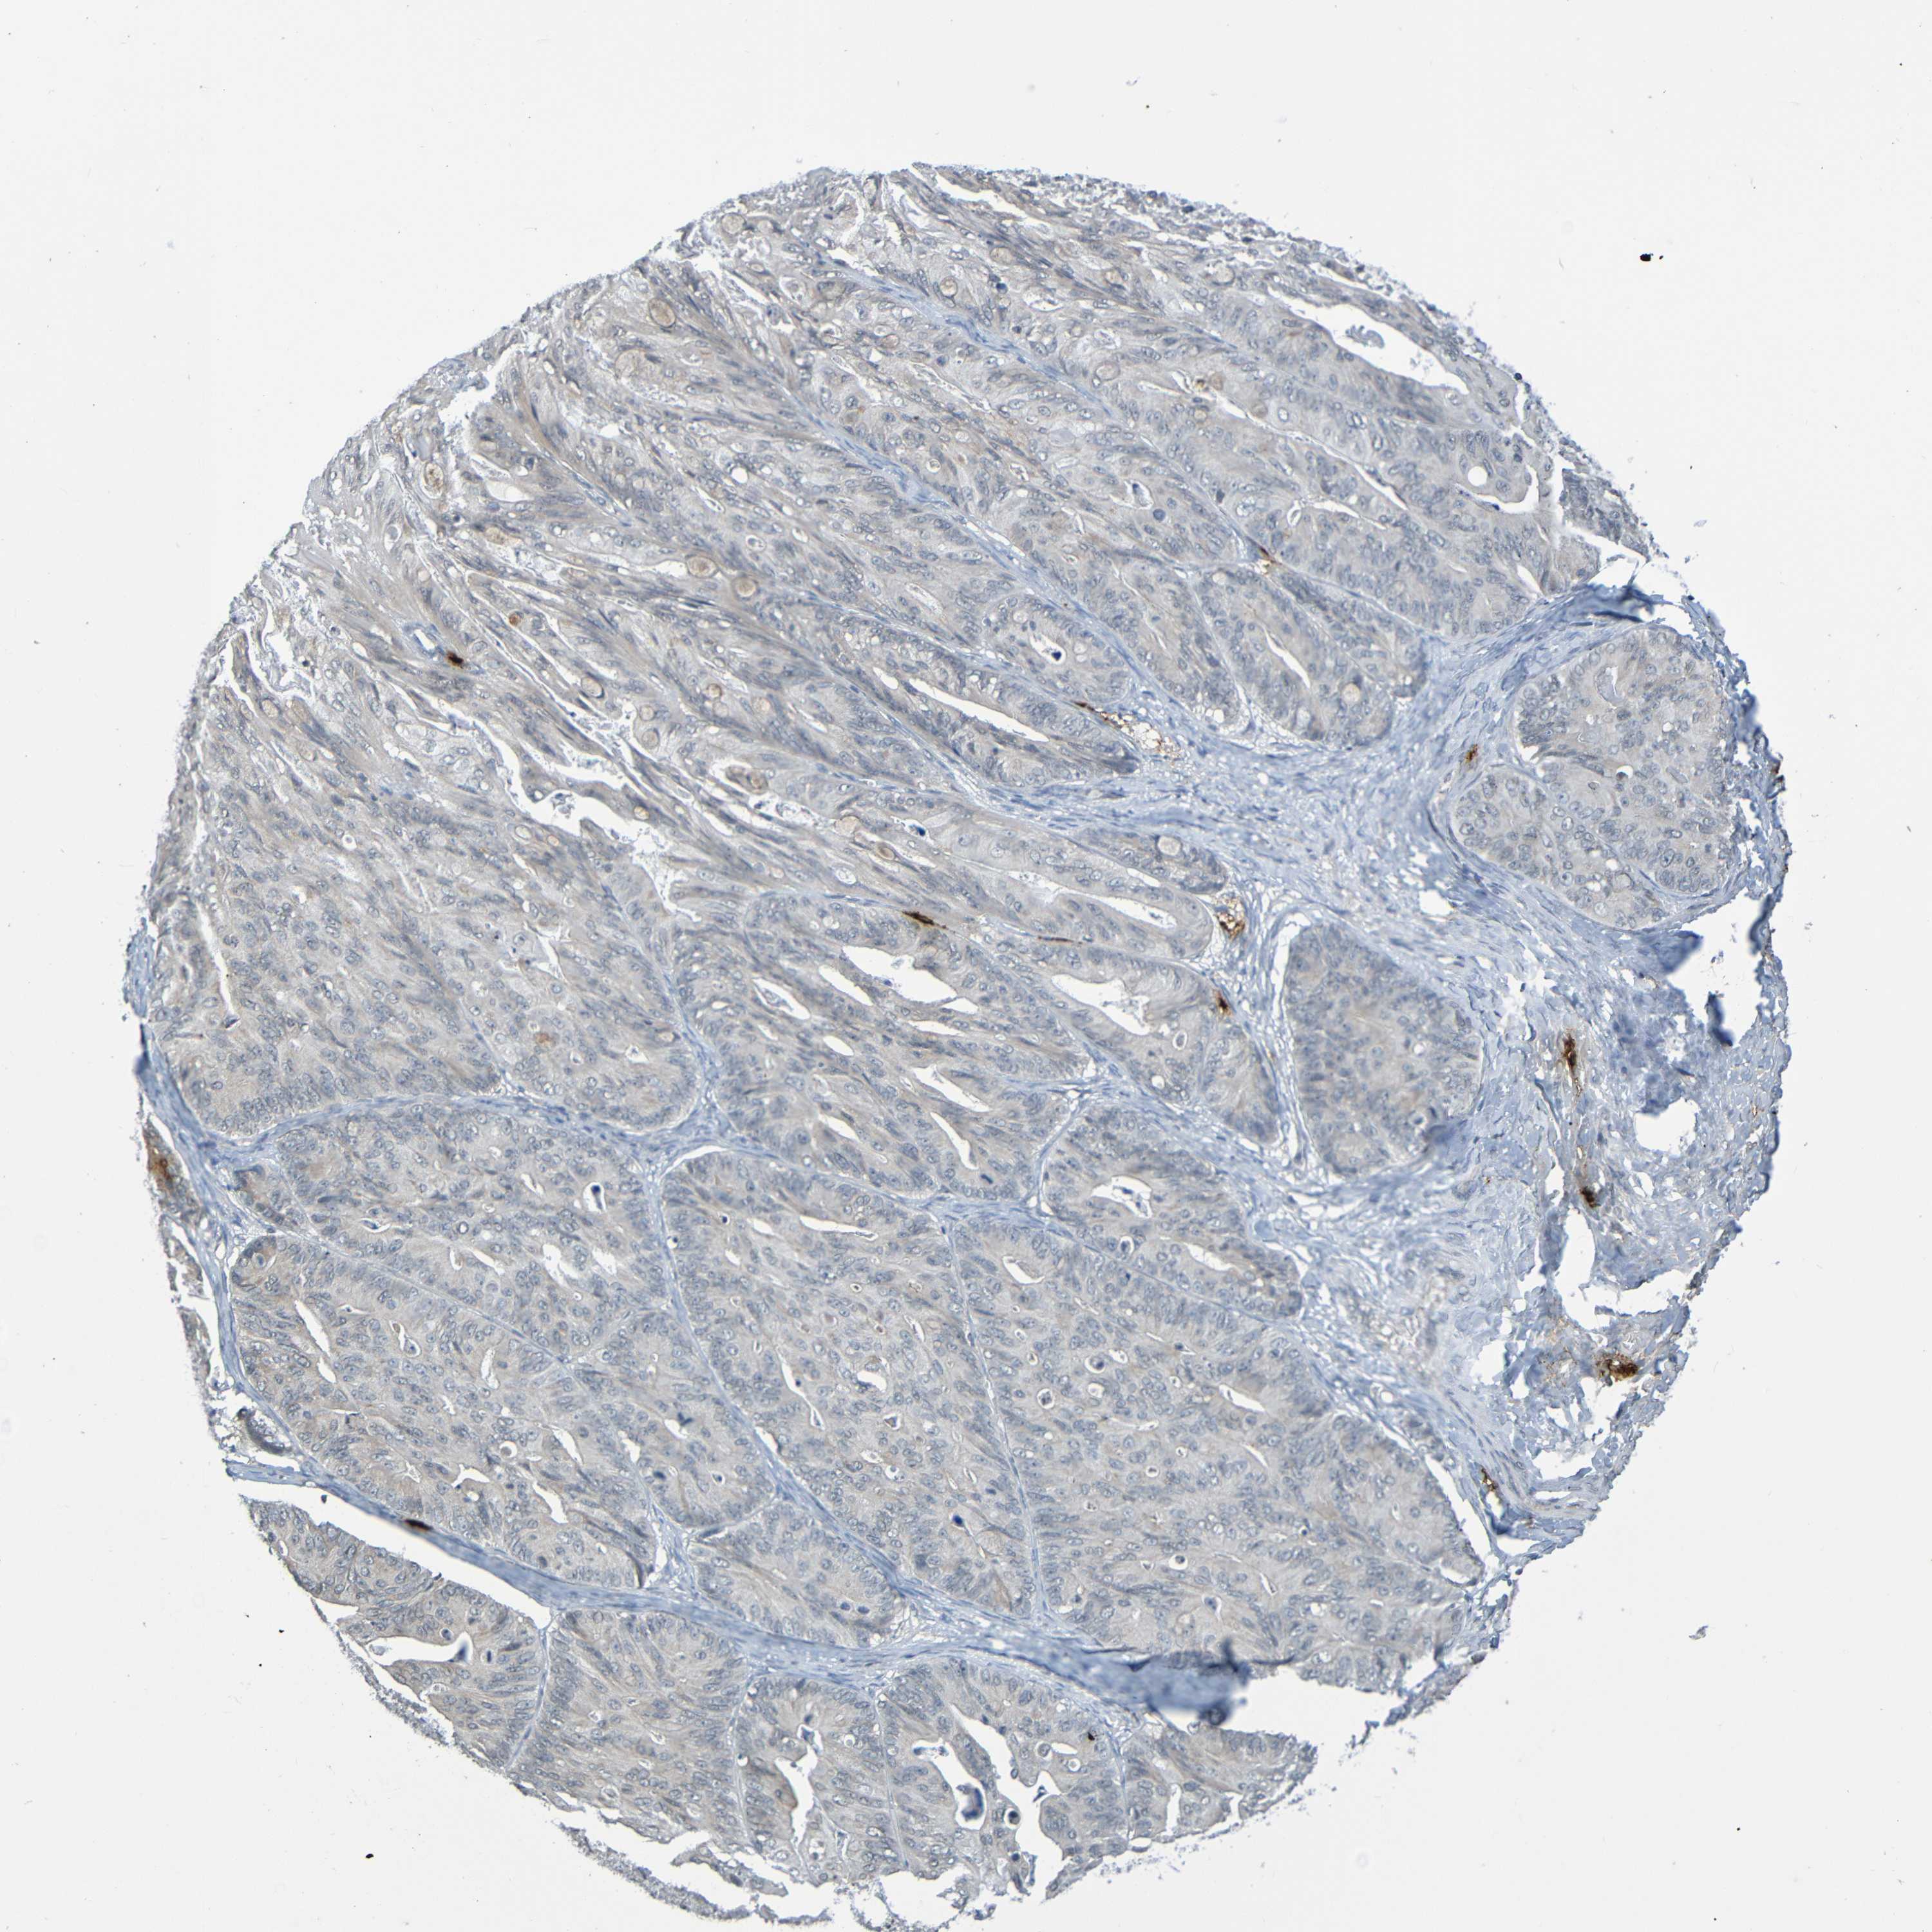

OVARIAN CANCER - Protein expressioni

A mouse-over function shows sample information and annotation data. Click on an image to view it in a full screen mode. Samples can be filtered based on level of antibody staining by selecting one or several of the following categories: high, medium, low and not detected. The assay and annotation is described here.

Note that samples used for immunohistochemistry by the Human Protein Atlas do not correspond to samples in the TCGA dataset.

Antibody stainingi

Antibody staining in the annotated cell types in the current human tissue is reported as not detected, low, medium, or high, based on conventional immunohistochemistry profiling in selected tissues. This score is based on the combination of the staining intensity and fraction of stained cells.

Each image is clickable and will lead to virtual microscopy that enables deeper exploration of all samples and also displays staining intensity scores, fraction scores and subcellular localization as well as patient and tissue information for each sample.

Antibody CAB009405

Staining

High

Medium

Low

Not detected

Intensity

Strong

Moderate

Weak

Negative

Quantity

>75%

75%-25%

<25%

None

Location

Nuclear

Cytoplasmic/membranous

Cytoplasmic/membranous,nuclear

Cystadenocarcinoma, serous, NOS

Carcinoma, endometroid

Cystadenocarcinoma, mucinous, NOS

Carcinoma, NOS